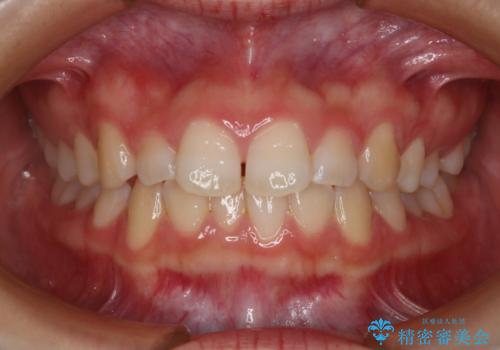

- 前歯のガタつきの改善を主訴に来院された患者様です。

ガタつきによる上顎正中の空隙や歯の突出感も気にされていました。

費用を抑えたいとの事だったので歯の移動量なども考慮し、インビザライン・ライトパッケージでの治療を計画しました。